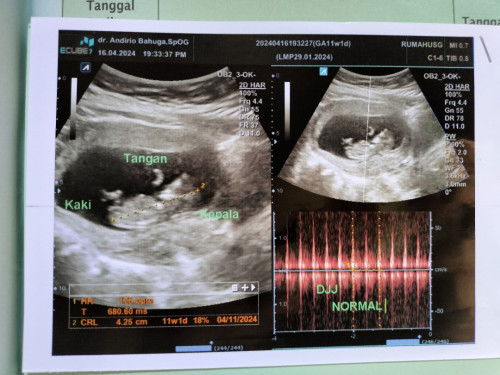

Usg 11 weeks

Bun mau tanya aku kan USG pertama UK 11 weeks udah ada janinnya dan detak jntungnya, tapi ini aku udah 13weeks tp kok perut msih belum keras sama sekali ya? Apakah wajar Bun??